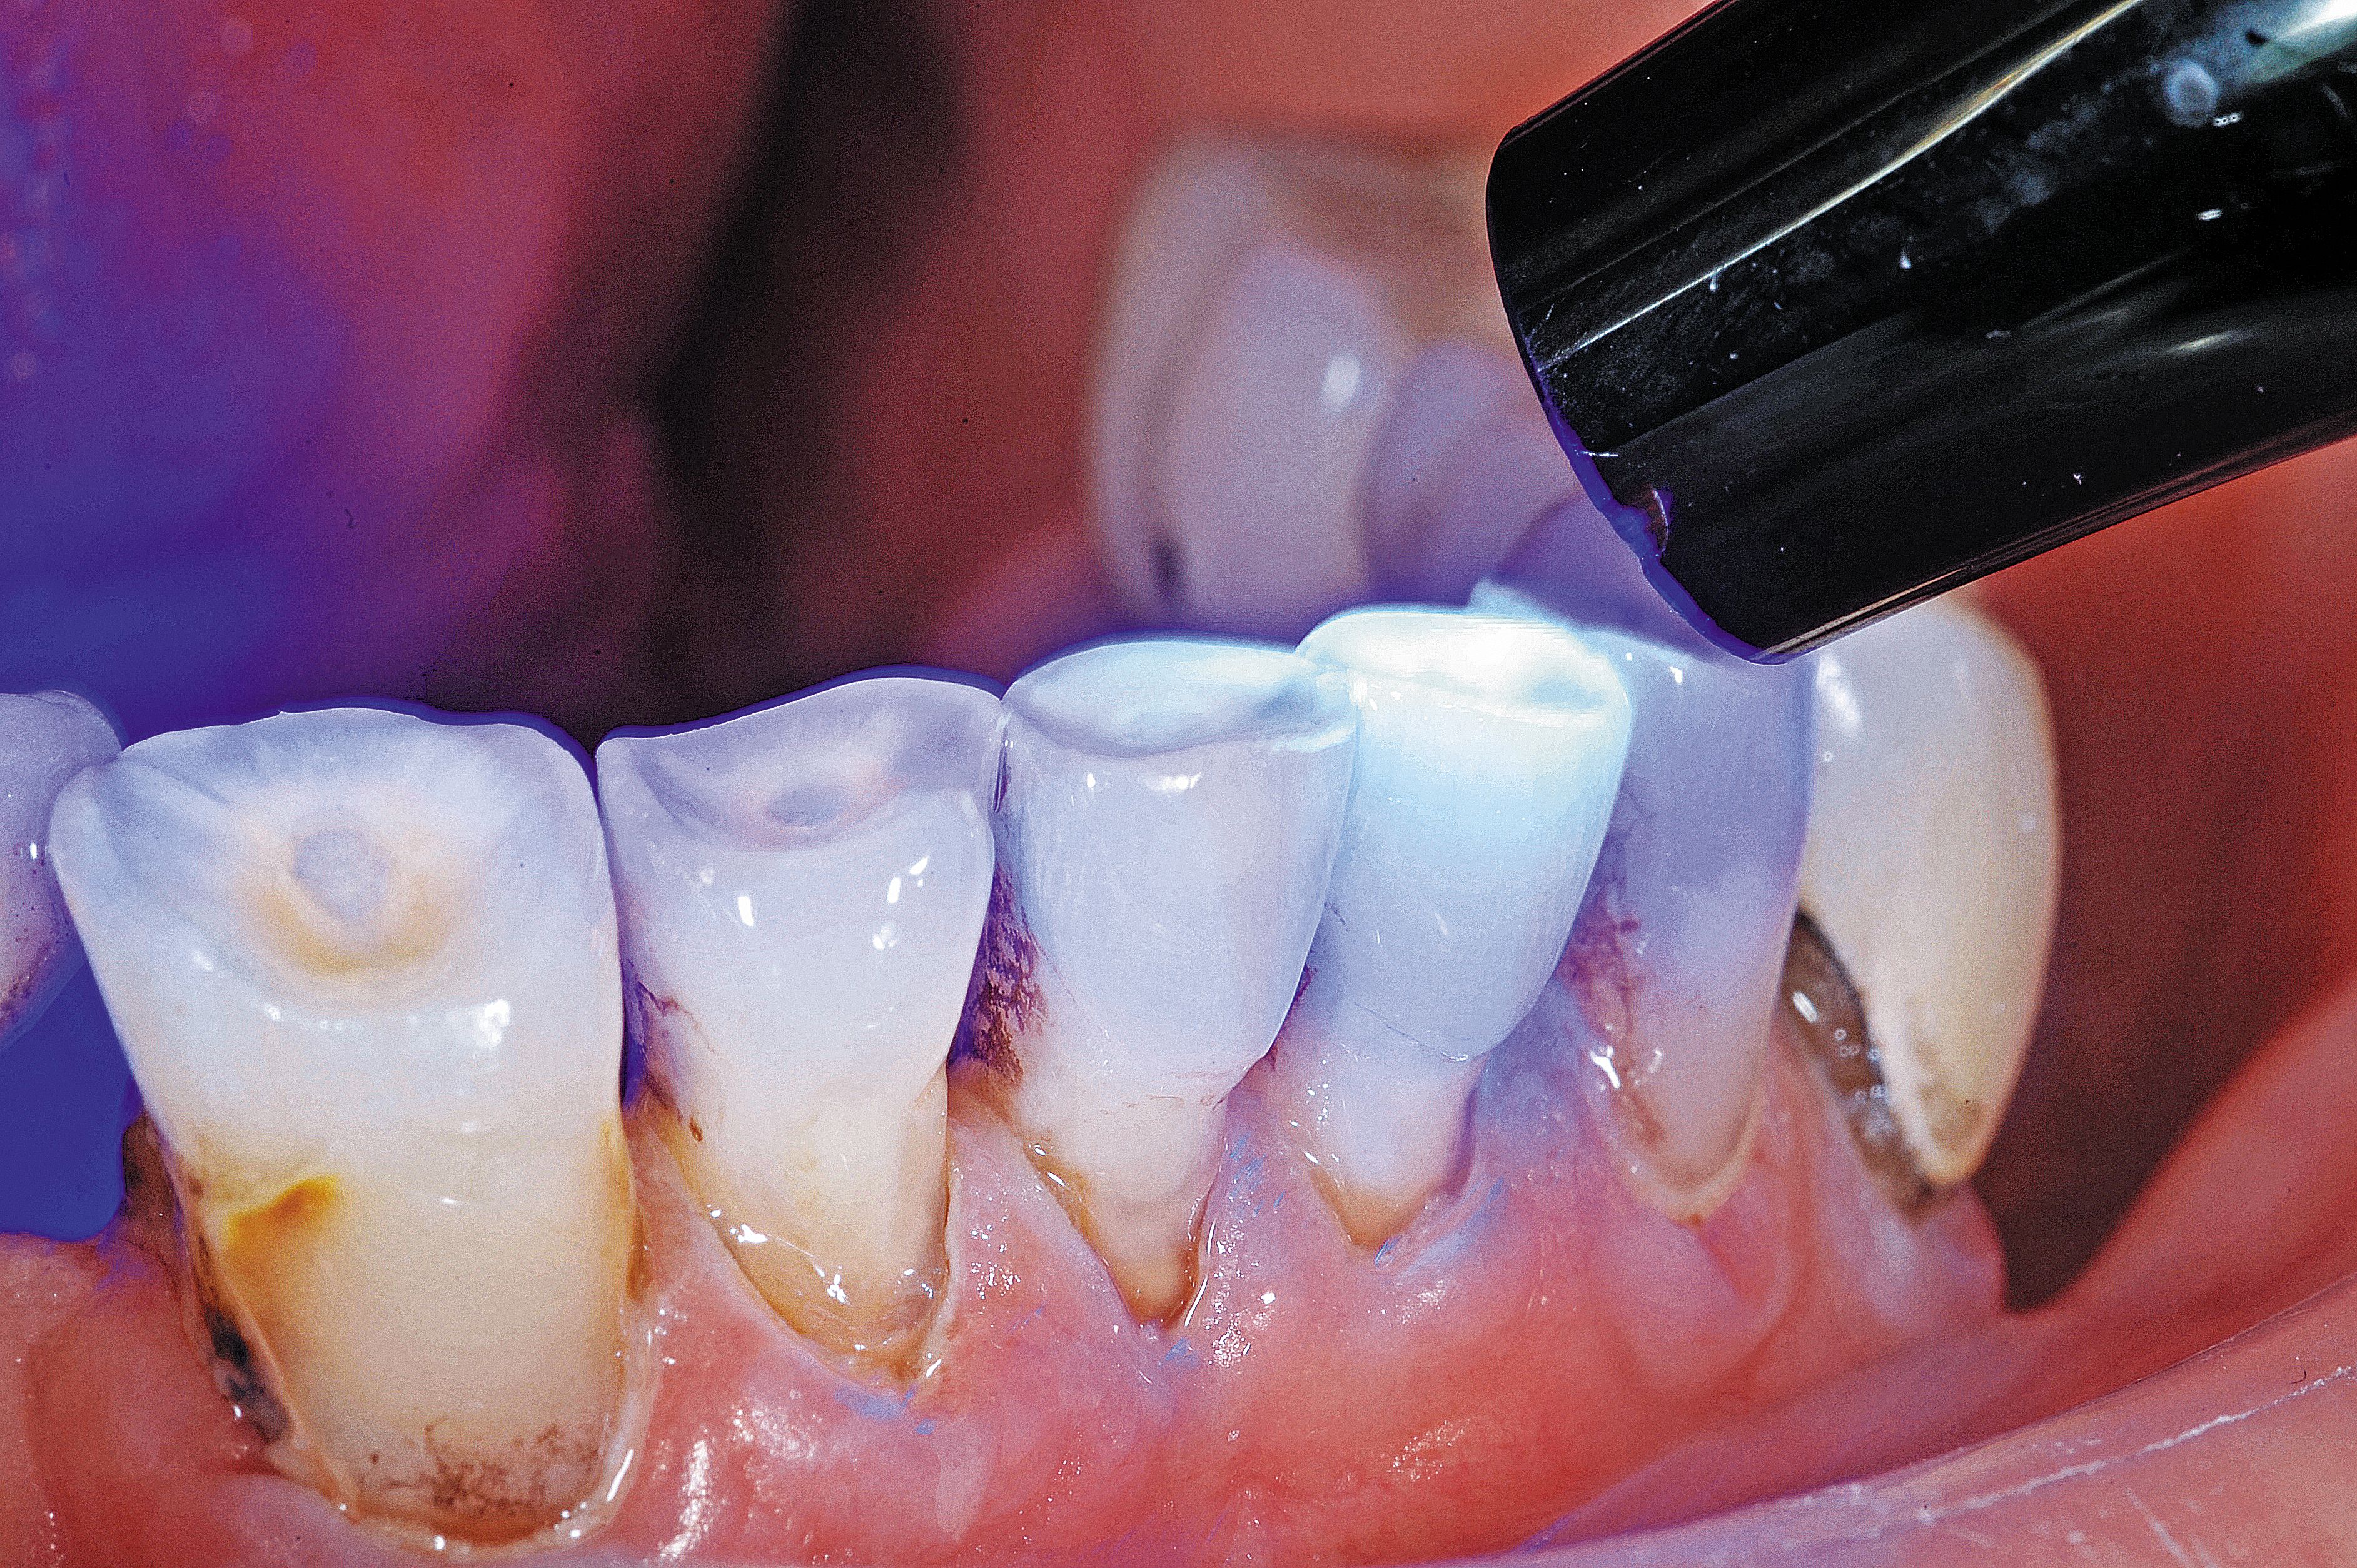

Fig. 1

In this case, the elderly gentleman had worn an upper denture for more than 50 years and was experiencing sensitivity to touch on the incisal edges of tooth Nos. 26 and 27. There was cold sensitivity on the lower incisor abfraction areas as well. There was also recurrent decay around the facial composite on the lower right bicuspid. He has been a chlorhexidine rinse user twice a day for more than 10 years, and staining was an ongoing issue (Fig. 1).